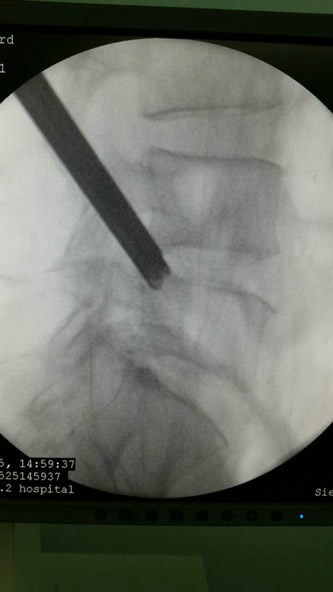

目前微创手术为脊柱外科的发展趋势,我院骨二科在魏人前主任带领下率先开展椎间孔内镜下腰椎间盘摘除术,通过靶点或精准穿刺到椎管。切口位于棘突旁开10-12cmm部位,切口大小1cm,用7.5mm管道经过椎间孔到达突出椎间盘处,插入内窥镜,在直视下行突出的髓核组织摘除,直接减压神经根,对椎管骚扰少。术后2小时后就可自行下床活动,一般住院2-3天出院。